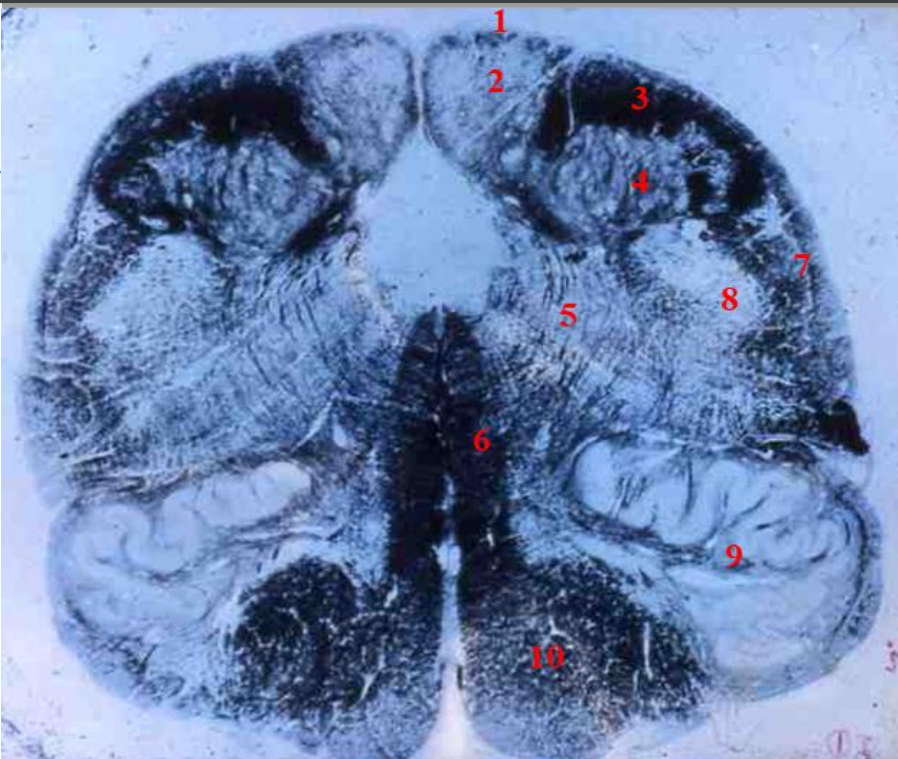

Q

A

cervical cord

- fibre tracts are larger

- grey matter is large

- brachial plexus

- no lateral horn

12

1

fasiculus gracilis

13

2

fasciculus cuneatus

14

3

posterior horn

15

4

anterior horn